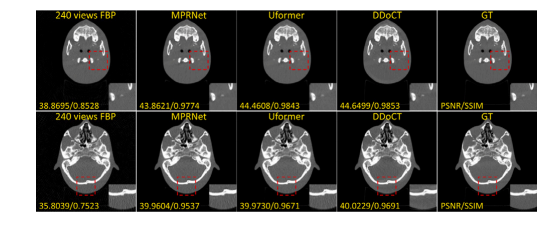

Fig. 6. Comparison of visual (together with quantitative results of PSNR and SSIM)images of the anthropomorphic head phantom dataset, which comprises pairs of CTimages acquired using on-board CBCT scanner with low-dose (80 kV, 100 mA) andhigh-dose (80 kV, 400 mA) settings, respectively. The set range of the display windowis a window level of 500 HU and a window width of 3000 HU (i.e., a range from−1000 HU to 2000 HU)

图6. 仿人头部模体数据集图像的视觉效果对比(包括PSNR和SSIM的定量结果)。该数据集包含使用机载CBCT扫描仪分别在低剂量(80 kV,100 mA)和高剂量(80 kV,400 mA)设置下获取的CT图像对。显示窗口的设置范围为窗位500 HU,窗宽3000 HU(即范围为−1000 HU到2000 HU)。